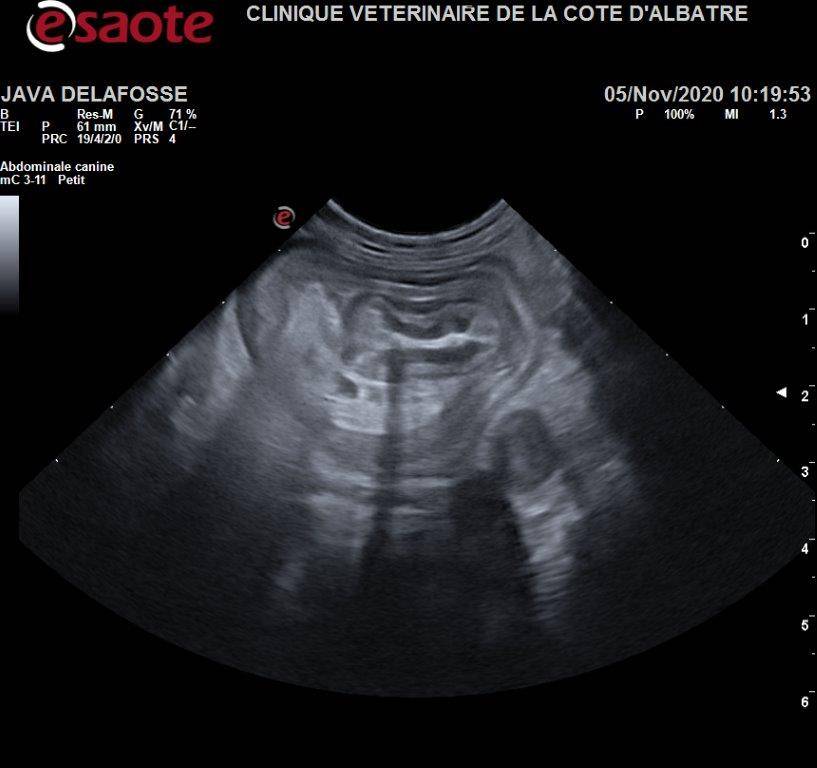

L'ingestion de corps étranger est fréquente chez les carnivores domestiques. Les symptômes peuvent être très variés : vomissements aigues ou chroniques, diarrhée, absence de selles, douleurs abdominales plus ou moins marquées, traces de sang dans les selles, dysorexie ou anorexie totale, amaigrissement rapide. La gravité des lésions intestinales occasionnées par le corps étranger est liée au corps étranger lui même (objets perforants, objets linéaires) et à sa localisation dans le système digestif (occlusion totale ou partielle ?). La visualisation en imagerie peut être difficile et demande souvent la combinaison de radiographies, d'échographies voire de la réalisation d'une succession de radiographies sur plusieurs heures appelée transit baryté (ingestion d'un produit de contraste visible à la radiographie dont on suit l'avancée dans le système digestif).